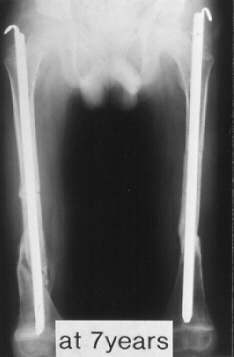

Case 3.

A 14-years-old boy. Body height 124 cm. Sillence type sporadic.

The first visit was at 2 years-old. He sustained one fracture in U/E and 8 fractures in L/E, underwent 10 operations, and has 60 degrees scoliosis. He became able to walk on crutches at 2 years old and had been a practical ambulator until 12 years old. He sustained a fracture at the distal end of right femur where an intramedullaly nail did not reached. He uses a wheelchair for long distant transportation. This case is supposed to be on the border line between ambulator and non-ambulator. The diameter of the femur was 10 mm at 3 years of age and 11mm at 13 years of age. No increase of diameter has been observed despite rather thin intramedullaly nailing.